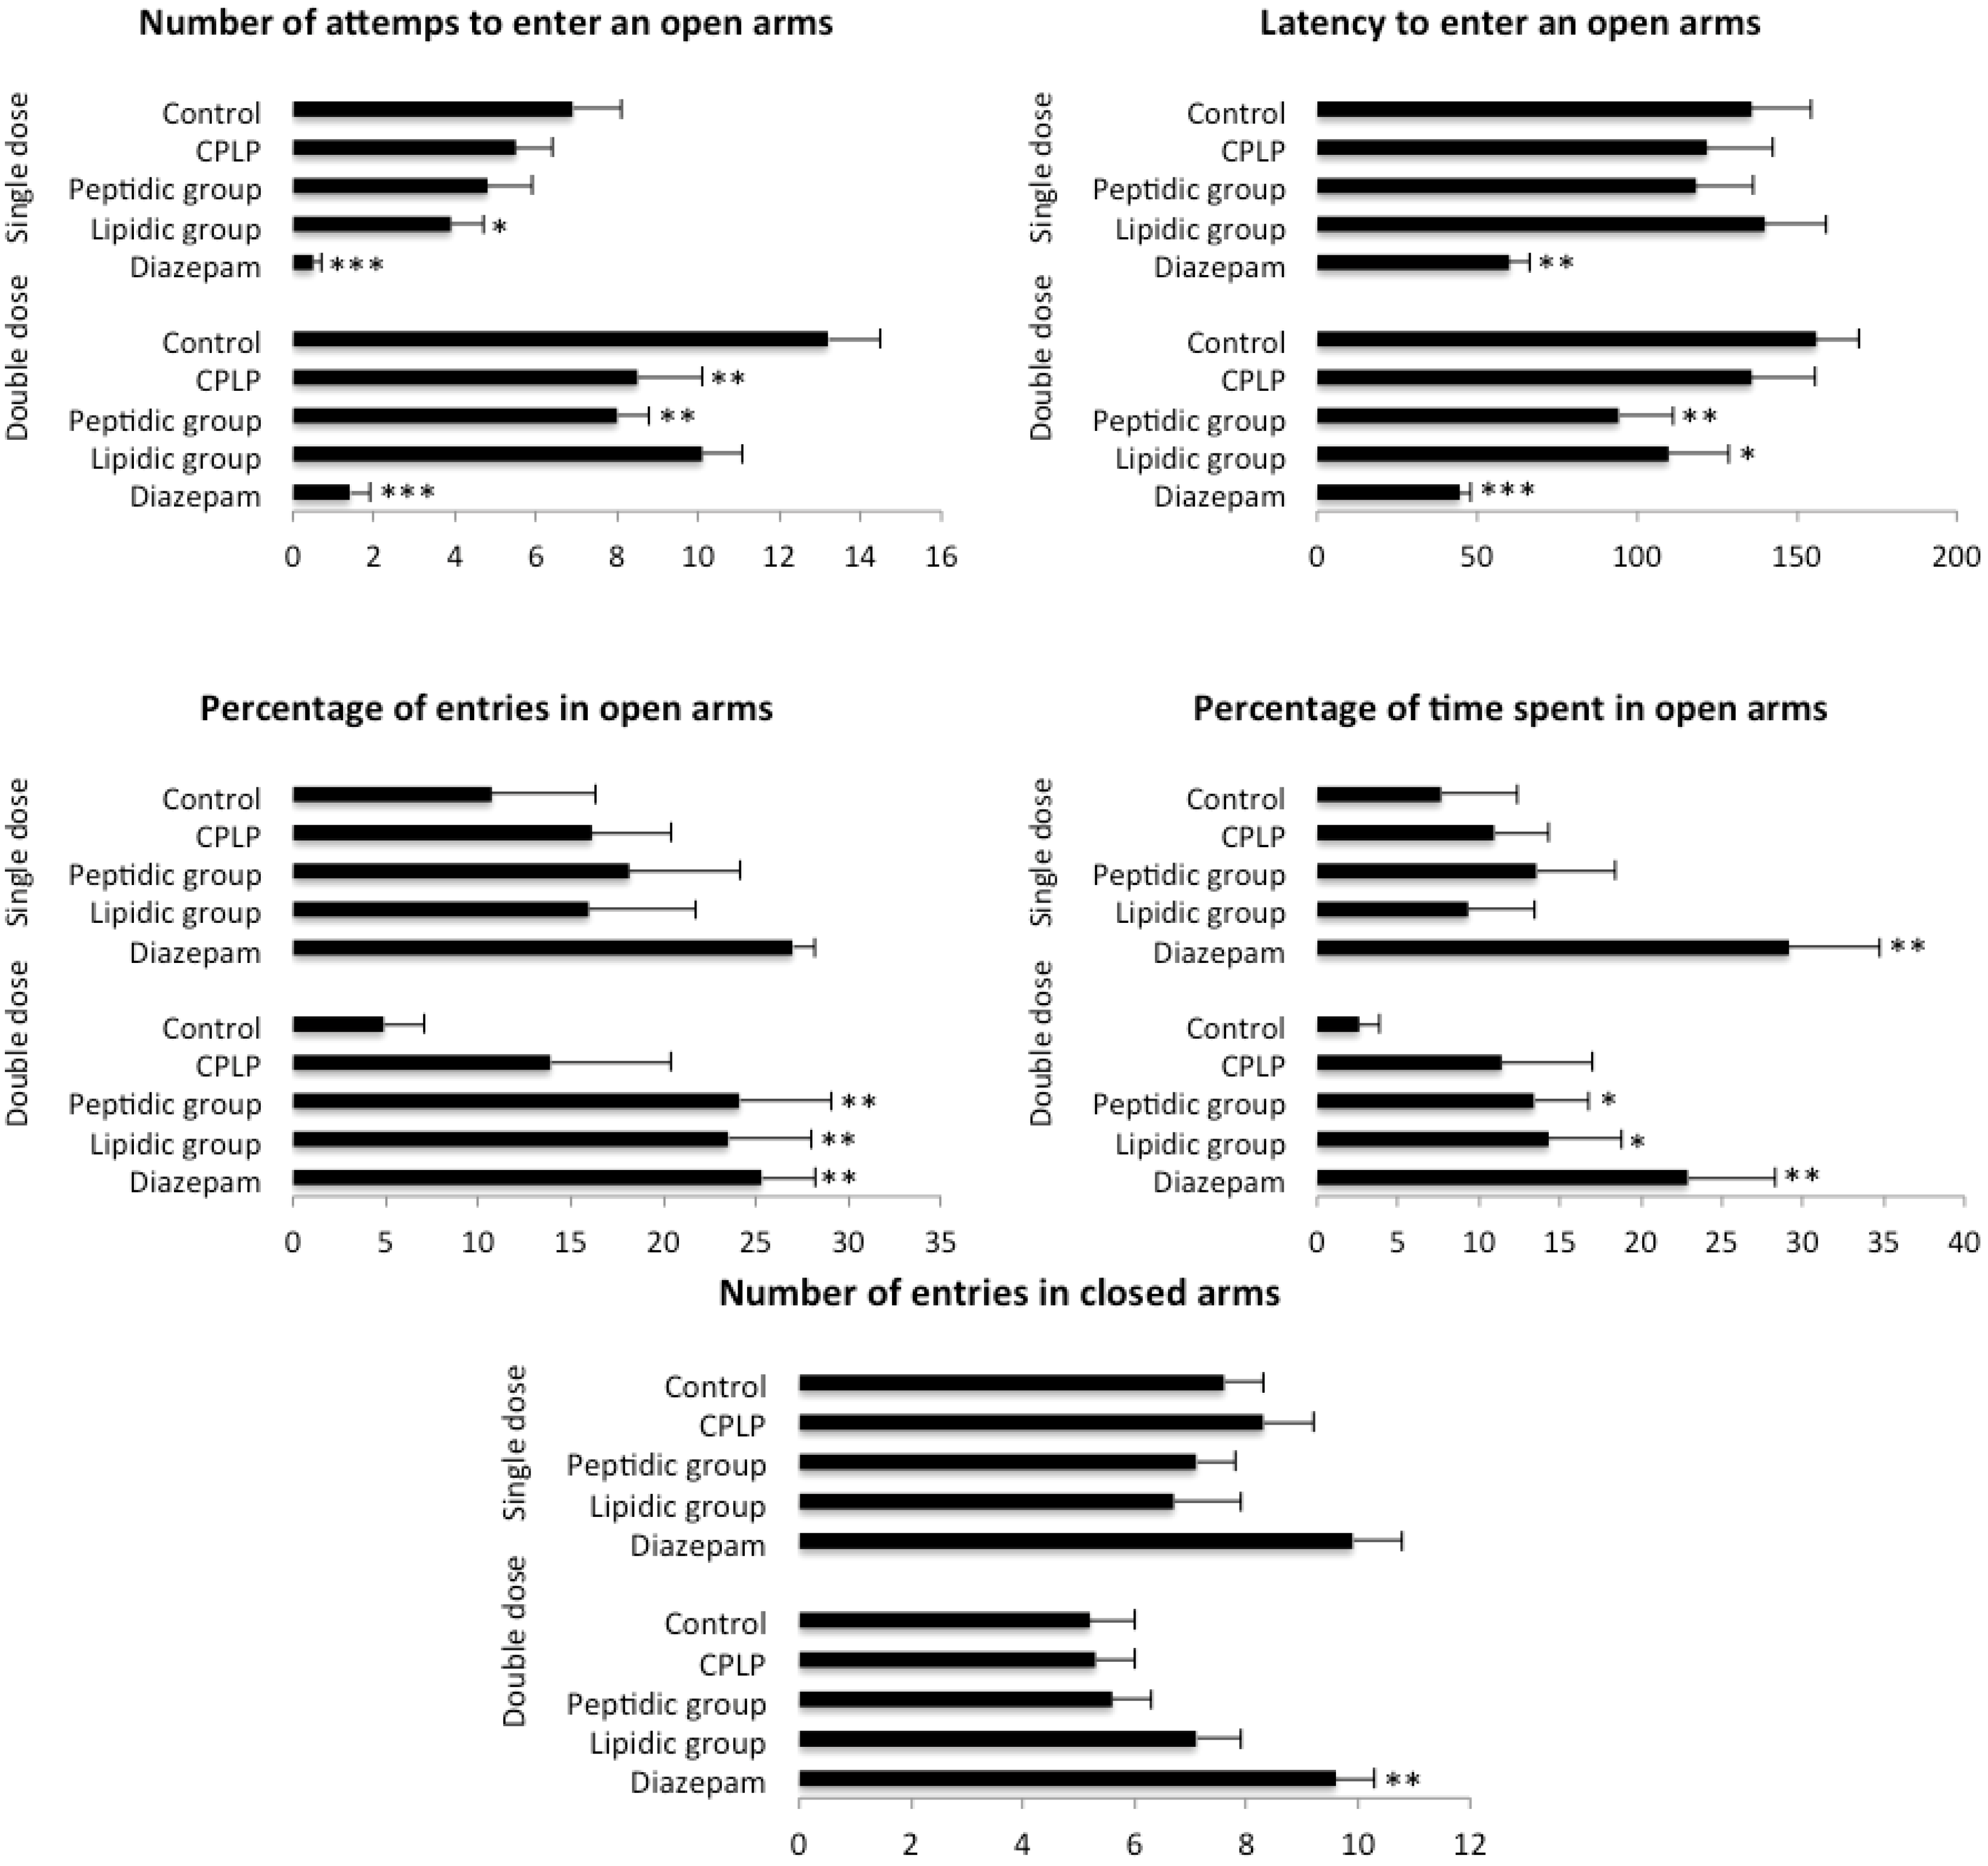

2.2.2. Behavioral Test

2.2.2.1. Elevated plus Maze (EPM)

4.3.3.1. Elevated Plus Maze (EPM)